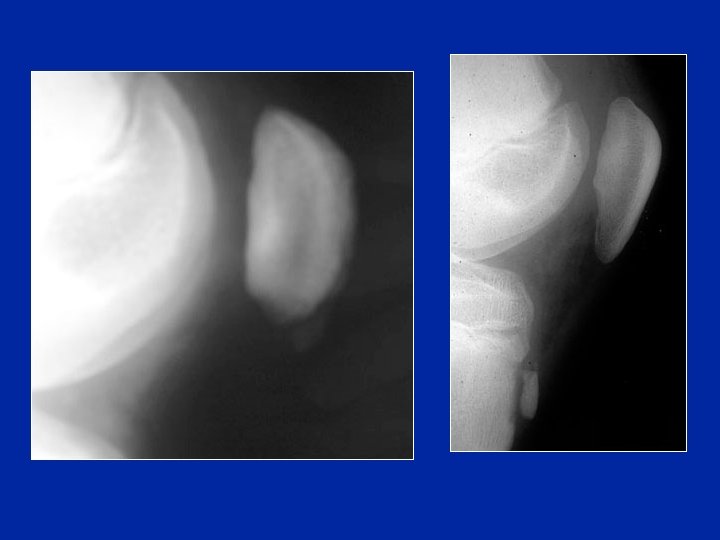

Osgood: radiología • • Contorno “impreciso” del rostro epifisiario Aspecto desgastado de la epífisis sub-condral Cuerpos extraños intra-tendinosos Fragmentación de la zona de inserción del tendón, correspondiente a los microarrancamientos ósteo-periósticos. • Desplazamiento anterior de la extremidad rostral de la epífisis • Los arrancamientos completos son raros • RMN: Edema del tendón rotuliano

Aspectos radiológicos (de perfil) rayos blandos

Enfermedad de Sinding-Larsen. Johansen

Enfermedad de Sinding-Larsen. Johansen • “Osgood” de la punta de la rótula (núcleo de osificación apical) • Tracción del tendón rotuliano • Esta enfermedad afecta sobre todo a los niños de 10 a 13 años. El presenta dolores mecánicos durante el esfuerzo.

Aspectos clínicos y radiográficos • Sintomatología parecida al Osgood • Posible confusión con un síndrome rotuliano • Dolor preciso a la compresión de la punta de la rótula. • Radiografía: pequeñas modificaciones de la punta de la rótula y a veces se observa un pequeño fragmento desprendido.

La evolución es favorable después del reposo. La evolución es lenta, y dura de 12 a 18 meses. Evolución radiológica favorable E Brunet-Guedj

Secuelas Las secuelas son raras, y ellas son morfológicas. Modificación de la forma de la punta de la rótula que en ocasiones parece alargada: "rótula en gota" Radios E Brunet-Guedj

Secuela clásica: “la nariz”

Osteocondrosis de la rótula Fragmentación de la rótula. Curación 1 año más tarde.